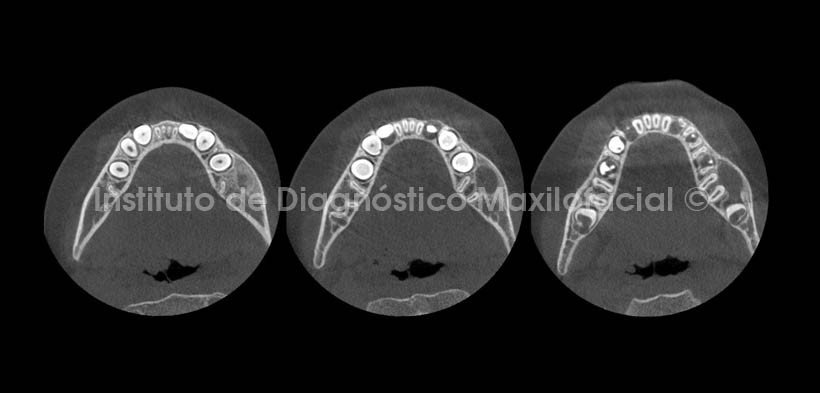

En cortes axiales y coronales (Fig.3 y 4), se observa el considerable aumento de volumen en el lado afectado, asi como el aumento de la densidad osea circundante ya mencionado y el adelgazamiento de la tabla osea vestibular a nivel del tercio cervical radicular (mas evidente en cortes axiales). Asi mismo, se observa la relación de la lesion con el germen dentario de la pieza 3.7.

La atenuación o la pérdida de la lámina dura alrededor de los ápices y en zona de furcación del diente afectado son signos radiográficos de esta lesión, presentando una zona radiolúcida de forma redondeada y limites definidos asociada al diente afectado. Así mismo, cuando la infección afecta el periostio, se observa radiográficamente la reacción del mismo como el aspecto de capas de cebolla, observándose con mayor claridad en incidencias oclusales y en tomográfia cone beam, sin embargo en la radiografía panorámica es posible evidenciar estos signos en relación con la basal mandibular. En estadios más avanzados se observa la considerable expansión del cuerpo mandibular conformada por zonas de aumento de la densidad ósea.